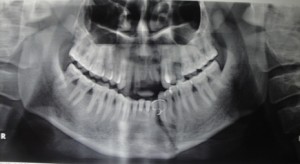

Правильной диагностике помогает рентгенологическое исследование. Так, прямая передняя обзорная рентгенограмма черепа дает представление о характере повреждений различной локализации. Боковые снимки тела и ветви нижней челюсти детализируют переломы в зоне премоляров, моляров, угла и ветви. При переломах мыщелковых отростков обязательно производят томограммы обоих височно-нижнечелюстных суставов в боковой проекции на глубине 2 см от поверхности стола.

Рентгенологически перелом нижней челюсти характеризуется наличием линии просветления, являющейся отображением плоскости перелома, имеющей линейный характер. Осколки чаще мелкие, образуются не всегда. В зоне приложения силы возникают обычно оскольчатые повреждения со сложным рисунком линии просветления. Локализация их нехарактерна. Смещение фрагментов возникает не только вследствие мышечной тяги, но и под воздействием прямой травмирующей силы. Следует учитывать взаимосвязь зубов с линией перелома, состояние периапикальных тканей зубов, находящихся вблизи зоны повреждения, и костных отделов пародонта на всем протяжении зубного ряда.

Среди одиночных переломов нижней челюсти преобладают повреждения в области угла. Плоскость перелома расположена под углом к средней сагиттальной плоскости черепа, наружная и внутренняя кортикальные пластинки повреждаются на разных уровнях, что создает иногда на рентгенограммах ложную картину оскольчатого повреждения. В центральных и боковых участках тела нижней челюсти преобладают смещения по вертикали. При переломах угла смещение невелико, обычно верхний фрагмент подтягивается краниально и поворачивается внутрь. При непрямых переломах в области ветви смещение верхнего фрагмента всегда проходит краниально и кнаружи. Большой фрагмент сдвигается в сторону перелома назад и кверху.

Косой и косовертикальный ход линии просветления говорит о повреждении ветви нижней челюсти. В этих случаях отломки смещаются друг относительно друга по ширине. При переломе обеих ветвей тело нижней челюсти нередко поворачивается вокруг поперечной оси. При этом центральные зубы могут занимать вентральное положение.

Переломы мыщелкового отростка делятся на переломы без смещения фрагментов, внутрисуставные и внесуставные, переломы шейки мыщелкового отростка со смещением фрагментов ротационного характера, когда верхний фрагмент поворачивается кнутри, и люксационные, при которых весь верхний фрагмент выходит из суставной впадины и располагается почти поперечно. О внутрисуставном переломе по рентгенологическим данным можно говорить с уверенностью лишь при переломах головки нижней челюсти.